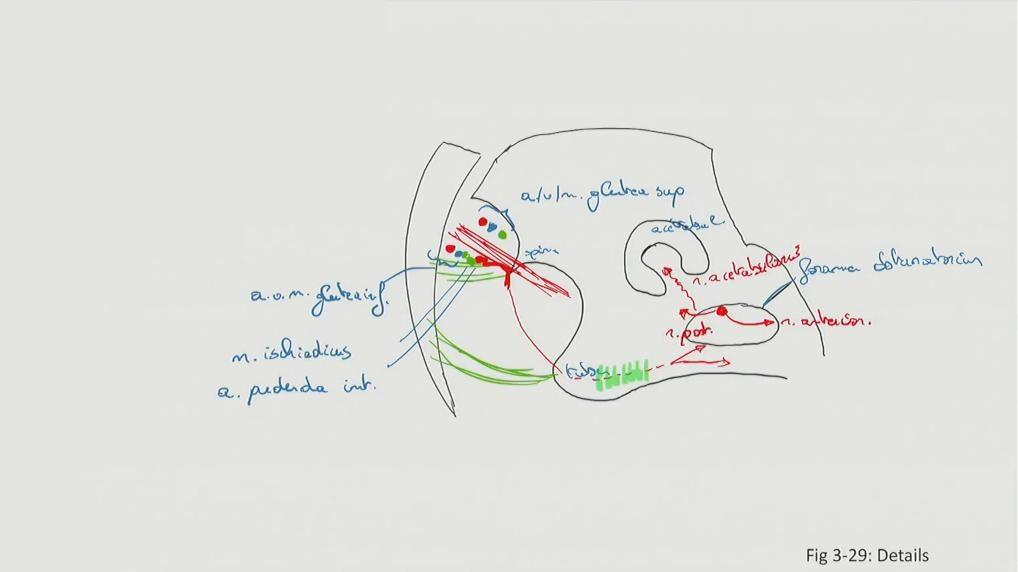

Fig 3.29b2: Details - os coxae

sacrum -

os coxae

lig sacrotuberale -

lig sacrospinale

|